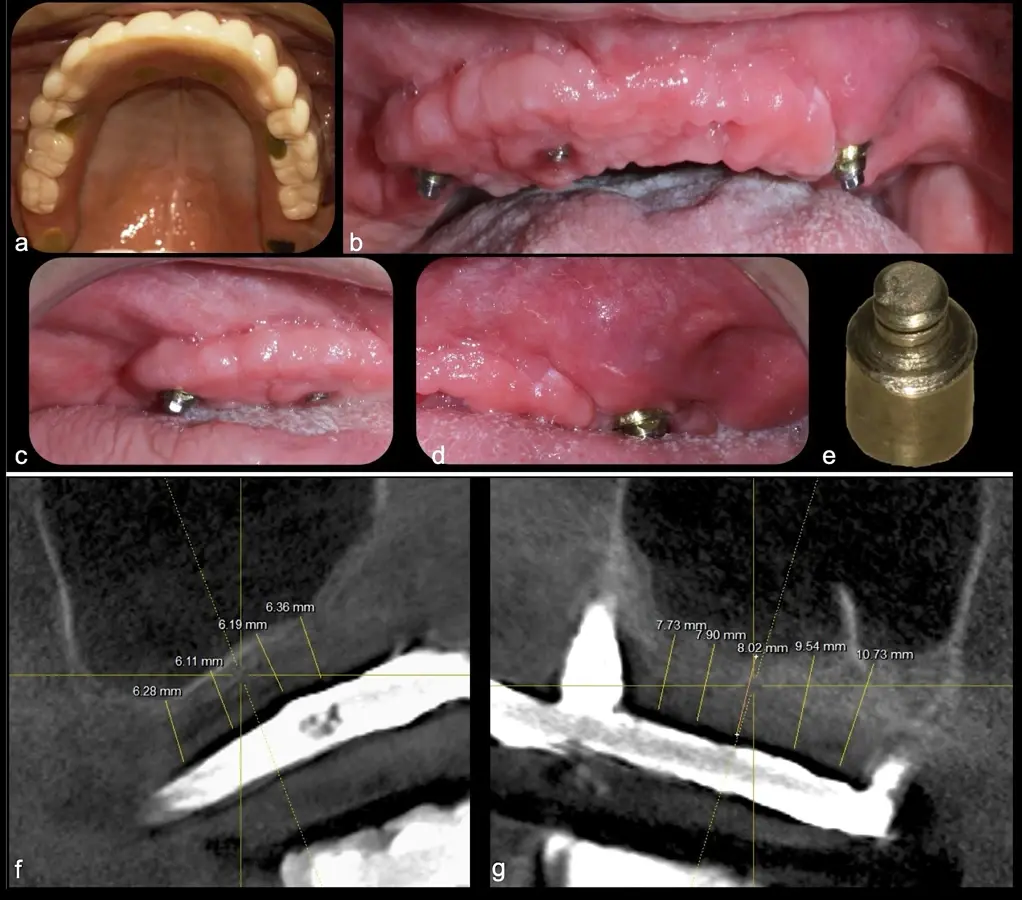

El levantamiento de piso de seno maxilar es una técnica quirúrgica aceptada previa o simultáneamente a la colocación de implantes dentales. La mayor evidencia científica refiere que si se tiene entre 0 -7 mm de altura ósea se debe realizar la elevación sinusal junto con injertos óseos; y a partir de los 8 mm, se hace más predecible la colocación simultánea de implantes dentales.1-3

Aunque esta técnica es predecible, la perforación de la membrana sinusal es la complicación intraoperatoria más común, con una prevalencia de hasta el 58.3%.4 Existen también otras complicaciones reportadas, como hemorragias asociadas a la lesión de la anastomosis arterial en el área de la pared lateral del seno maxilar.5-8

Estudios de síntesis bibliográficas con meta-análisis han descrito que el uso de instrumentos rotatorios convencionales está asociado a una tasa de perforación del 24% y con los dispositivos piezoeléctricos a un 8%, con una diferencia clínica y estadísticamente significativa entre ambas modalidades.17

El uso de instrumentos rotatorios convencionales está asociado a una tasa de perforación del 24% y con los dispositivos piezoeléctricos a un 8%, con una diferencia clínica y estadísticamente significativa entre ambas modalidades.

El clínico puede retirar la tabla ósea o introducirla como “tienda de campaña” dentro del seno maxilar. En cualquiera de las alternativas, es importante evaluar la presencia de tabiques óseos y de la arteria postero alveolar superior.